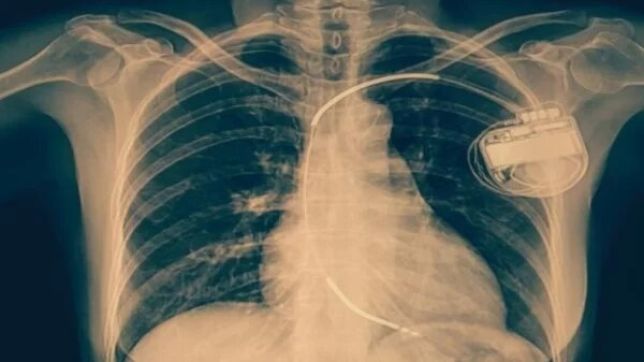

O Ministério Público do Distrito Federal e Territórios (MPDFT) emitiu recomendação para que o governo faça concurso público e convocação imediata de médicos cardiologistas. O parecer, enviado às secretarias de Saúde e de Economia, cita uma demanda de 14.685 consultas na fila. As pastas têm dez dias para enviar uma resposta, a partir do envio do documento, na última quinta-feira (14/3).

Estudos da 2ª Promotoria de Justiça de Defesa da Saúde (Prosus), do MPDFT, apontam déficit de 82 médicos cardiologistas com carga horária de 20 horas semanais na rede pública do Distrito Federal. Além disso, há 14.685 solicitações não atendidas, que são a soma de 7.768 consultas aguardando agendamento para a especialidade, mais outras 6.917 que foram devolvidas ao cardiologista para complementação de informações.

“Chegou ao conhecimento desta Promotoria de Justiça que há pacientes usuários do Serviço único de Saúde (SUS) no DF que estão aguardando há mais de cinco anos por consulta com médico cardiologista”, cita o Ministério Público, na recomendação.